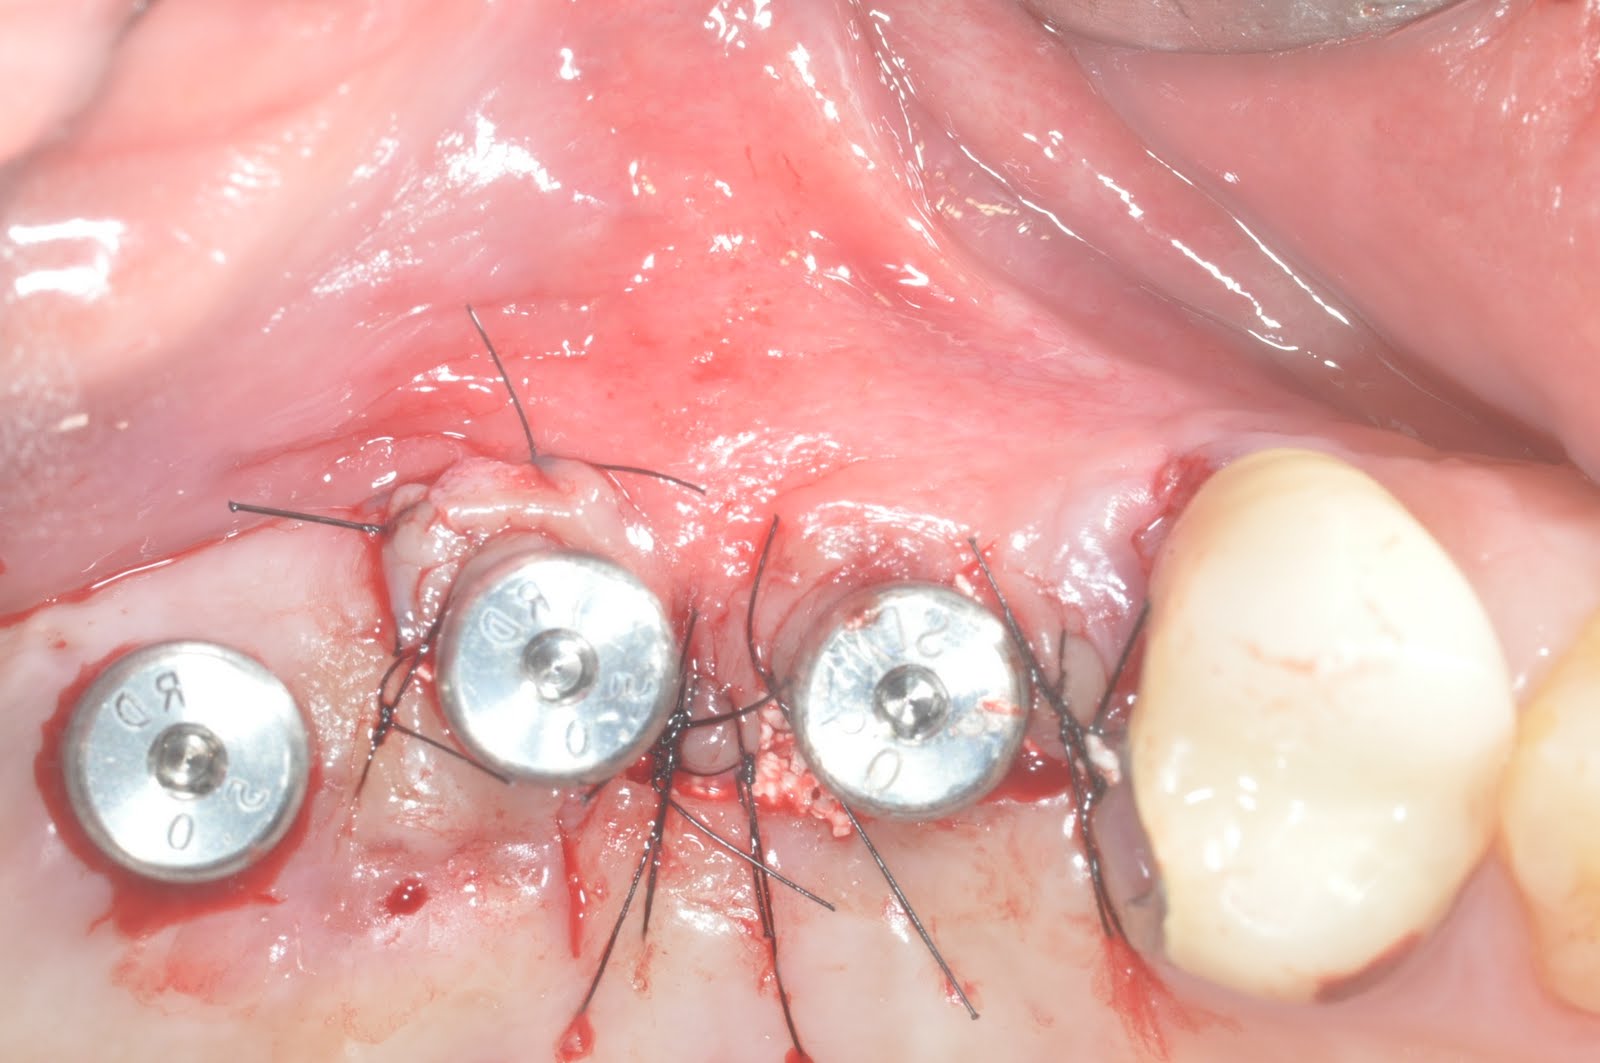

Dental Implant Sinus Membrane Perforation . Implant perforation of the maxillary sinus was defined as the intrusion of a dental implant into the sinus. Some early warning signs to watch out for include: A perforated sinus occurs when the implant penetrates the sinus membrane (schneiderian membrane), which separates the sinus from the upper jawbone. The aim of the present systematic review was to investigate the clinical outcomes after the perforation of the maxillary sinus by dental implants, or after maxillary. Sinus perforation after a dental implant can lead to serious complications if not detected early. The aim of this study was to estimate the incidence of sinus membrane perforation in maxillary sinus augmentation surgery using a lateral approach and the. A common complication of sinus augmentation is perforation of the sinus membrane during augmentation and/or implant placement. Perforation of the sinus membrane can result in dissemination of grafting material into the sinus cavity, potentially compromising.